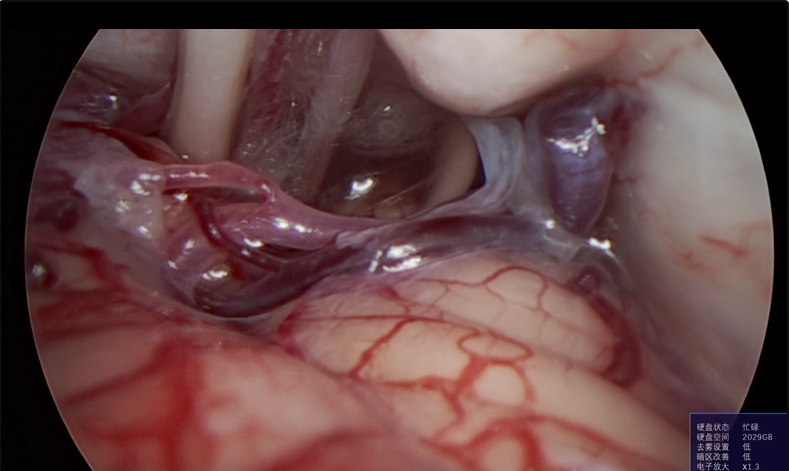

神经外科垂体瘤手术